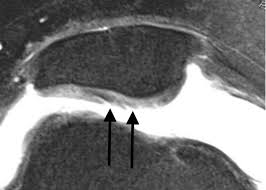

Clinicians who see patients with knee pain know the challenges of helping those with patellofemoral pain.

But how do we know which structures hurt the most? And does it change management?

In 1998, Dr Scott Dye decided to scope his own knee without anesthesia to find out. 😳

🧵👇 1/7Image From his previous work with patients he had observed:

🔹 Some had fibrillated cartilage but no pain -👇

🔹 Others had pristine cartilage but pain ++

It challenged the belief that cartilage damage alone = pain in PFJ syndromes & OA.

So he asked: Which structures actually "feel" pain? 2/7Image